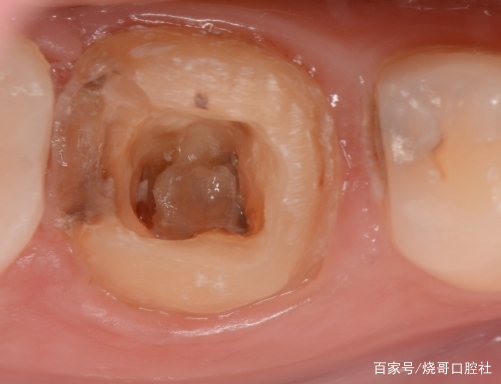

觀察牙齒癥狀

1、牙齒疼痛:當(dāng)牙齒出現(xiàn)牙洞并逐漸深入牙髓時,患者可能會感到牙齒疼痛,疼痛的性質(zhì)可能包括持續(xù)性鈍痛、陣發(fā)性疼痛等,尤其在咀嚼食物或受到冷熱刺激時更為明顯。

2、牙齒敏感:當(dāng)牙洞接近牙髓時,牙齒可能對溫度、壓力等刺激變得敏感,患者可能會感到不適。

3、牙齒變色:牙洞深入牙髓后,可能會導(dǎo)致牙齒顏色發(fā)生變化,如牙齒變黑或變黃。

1、口腔鏡檢查:通過口腔鏡檢查,可以清晰地觀察到牙齒表面的牙洞以及牙洞內(nèi)的情況,醫(yī)生可以判斷牙洞是否已深入牙髓,并評估病情嚴重程度。